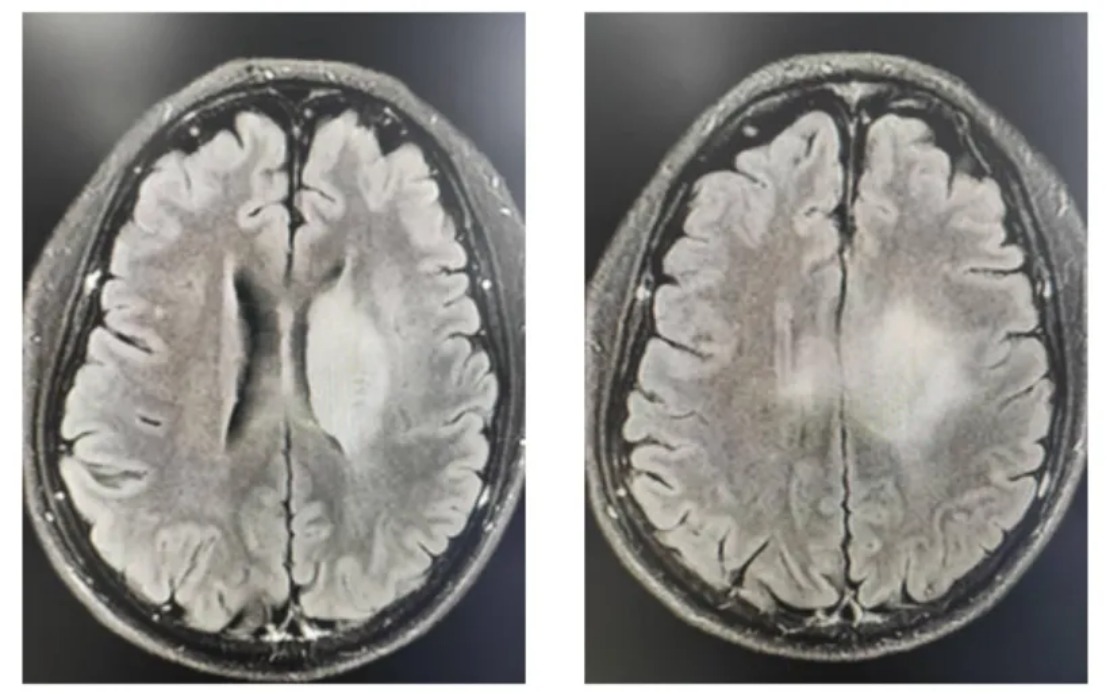

2024-07-18复查颅脑MR:对比2024-05-19 MR提示中脑不规则异常信号影,符合DMG治疗后改变,较前变化不大。左侧颞叶海马区、左侧丘脑、侧脑室旁条片状异常信号影,范围较前稍缩小(图5)。

2024-12-09复查颅脑MR:左侧颞叶海马区、左侧丘脑、侧脑室旁条片状异常信号影范围较前缩小(图6)。

图5 2024-07复查影像学

图6 2024-12-09 MR复查图